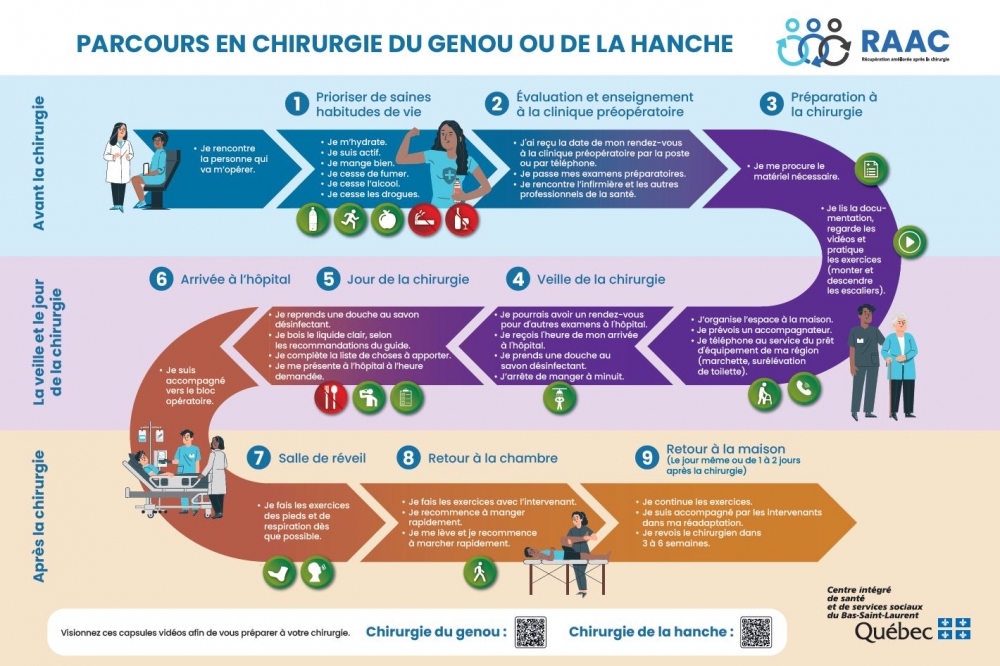

Pour compléter l'enseignement du professionnel, vous trouverez dans cette page un dépliant portant sur les consignes importantes avant la chirurgie, un parcours imagé des étapes avant, pendant et après la chirurgie, un livret d’enseignement essentiel à votre réadaptation ainsi que des vidéos préparatoires selon votre opération au genou ou à la hanche.

- Dépliant du parcours en chirurgie du genou ou de la hanche

- Dépliant du parcours en chirurgie du genou ou de la hanche

Au cours de la dernière année, le ministère de la Santé et des Services sociaux a entrepris des démarches visant à créer et à déployer des parcours cliniques de récupération améliorée après la chirurgie (RAAC) dans l'ensemble des établissements de santé du Québec.

Ultimement la RAAC vise à améliorer l’expérience des usagers et permettre un retour aux habitudes de vies quotidienne plus rapidement après une chirurgie.